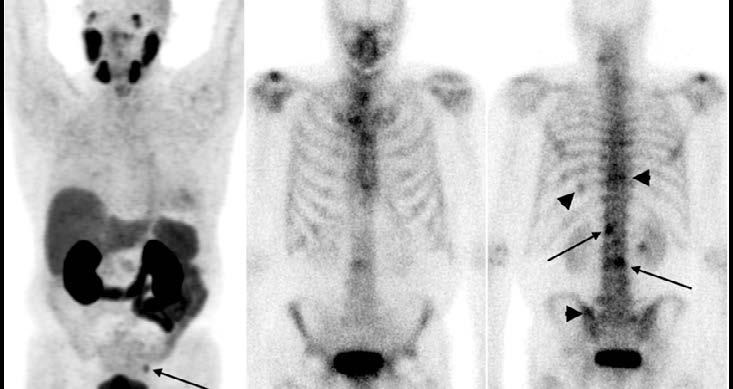

75 For Some Prostate Cancer Patients, PSMA PET May Be Better for Initial Staging of Disease